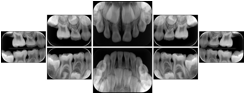

Intra-oral radiography typically involves acquisition of multiple images of various parts of the dentition. Many digital radiographic systems offer customized templates that are used for displaying the images in a study on the screen. These templates may also be referred to as mounts or view sets. The Structured Display Object represents a standard method of encoding and exchanging the layout and intended display of Structured Displays. A structured display object created in this manner could be stored with a study and exchanged with images to allow for complete reproduction of the original exam.

1. A patient visits a General Dentist where a Full Mouth Series Exam with 18 images is acquired. The dentist observes severe bone loss and refers the patient to a Periodontist. The 18 images from the Full Mouth Series along with a Structured Display are copied to a DICOM Interchange CD and sent with the patient to see the specialist. The Periodontist uses the CD to open the exam in his Dental Radiographic Software and consults via phone with the General Dentist. Both are able to observe the same exam showing the images on each user's display using the exact same layout.

Intra-oral Full Mouth Series Structured Display

Figure OO-1. Intra-oral Full Mouth Series Structured Display